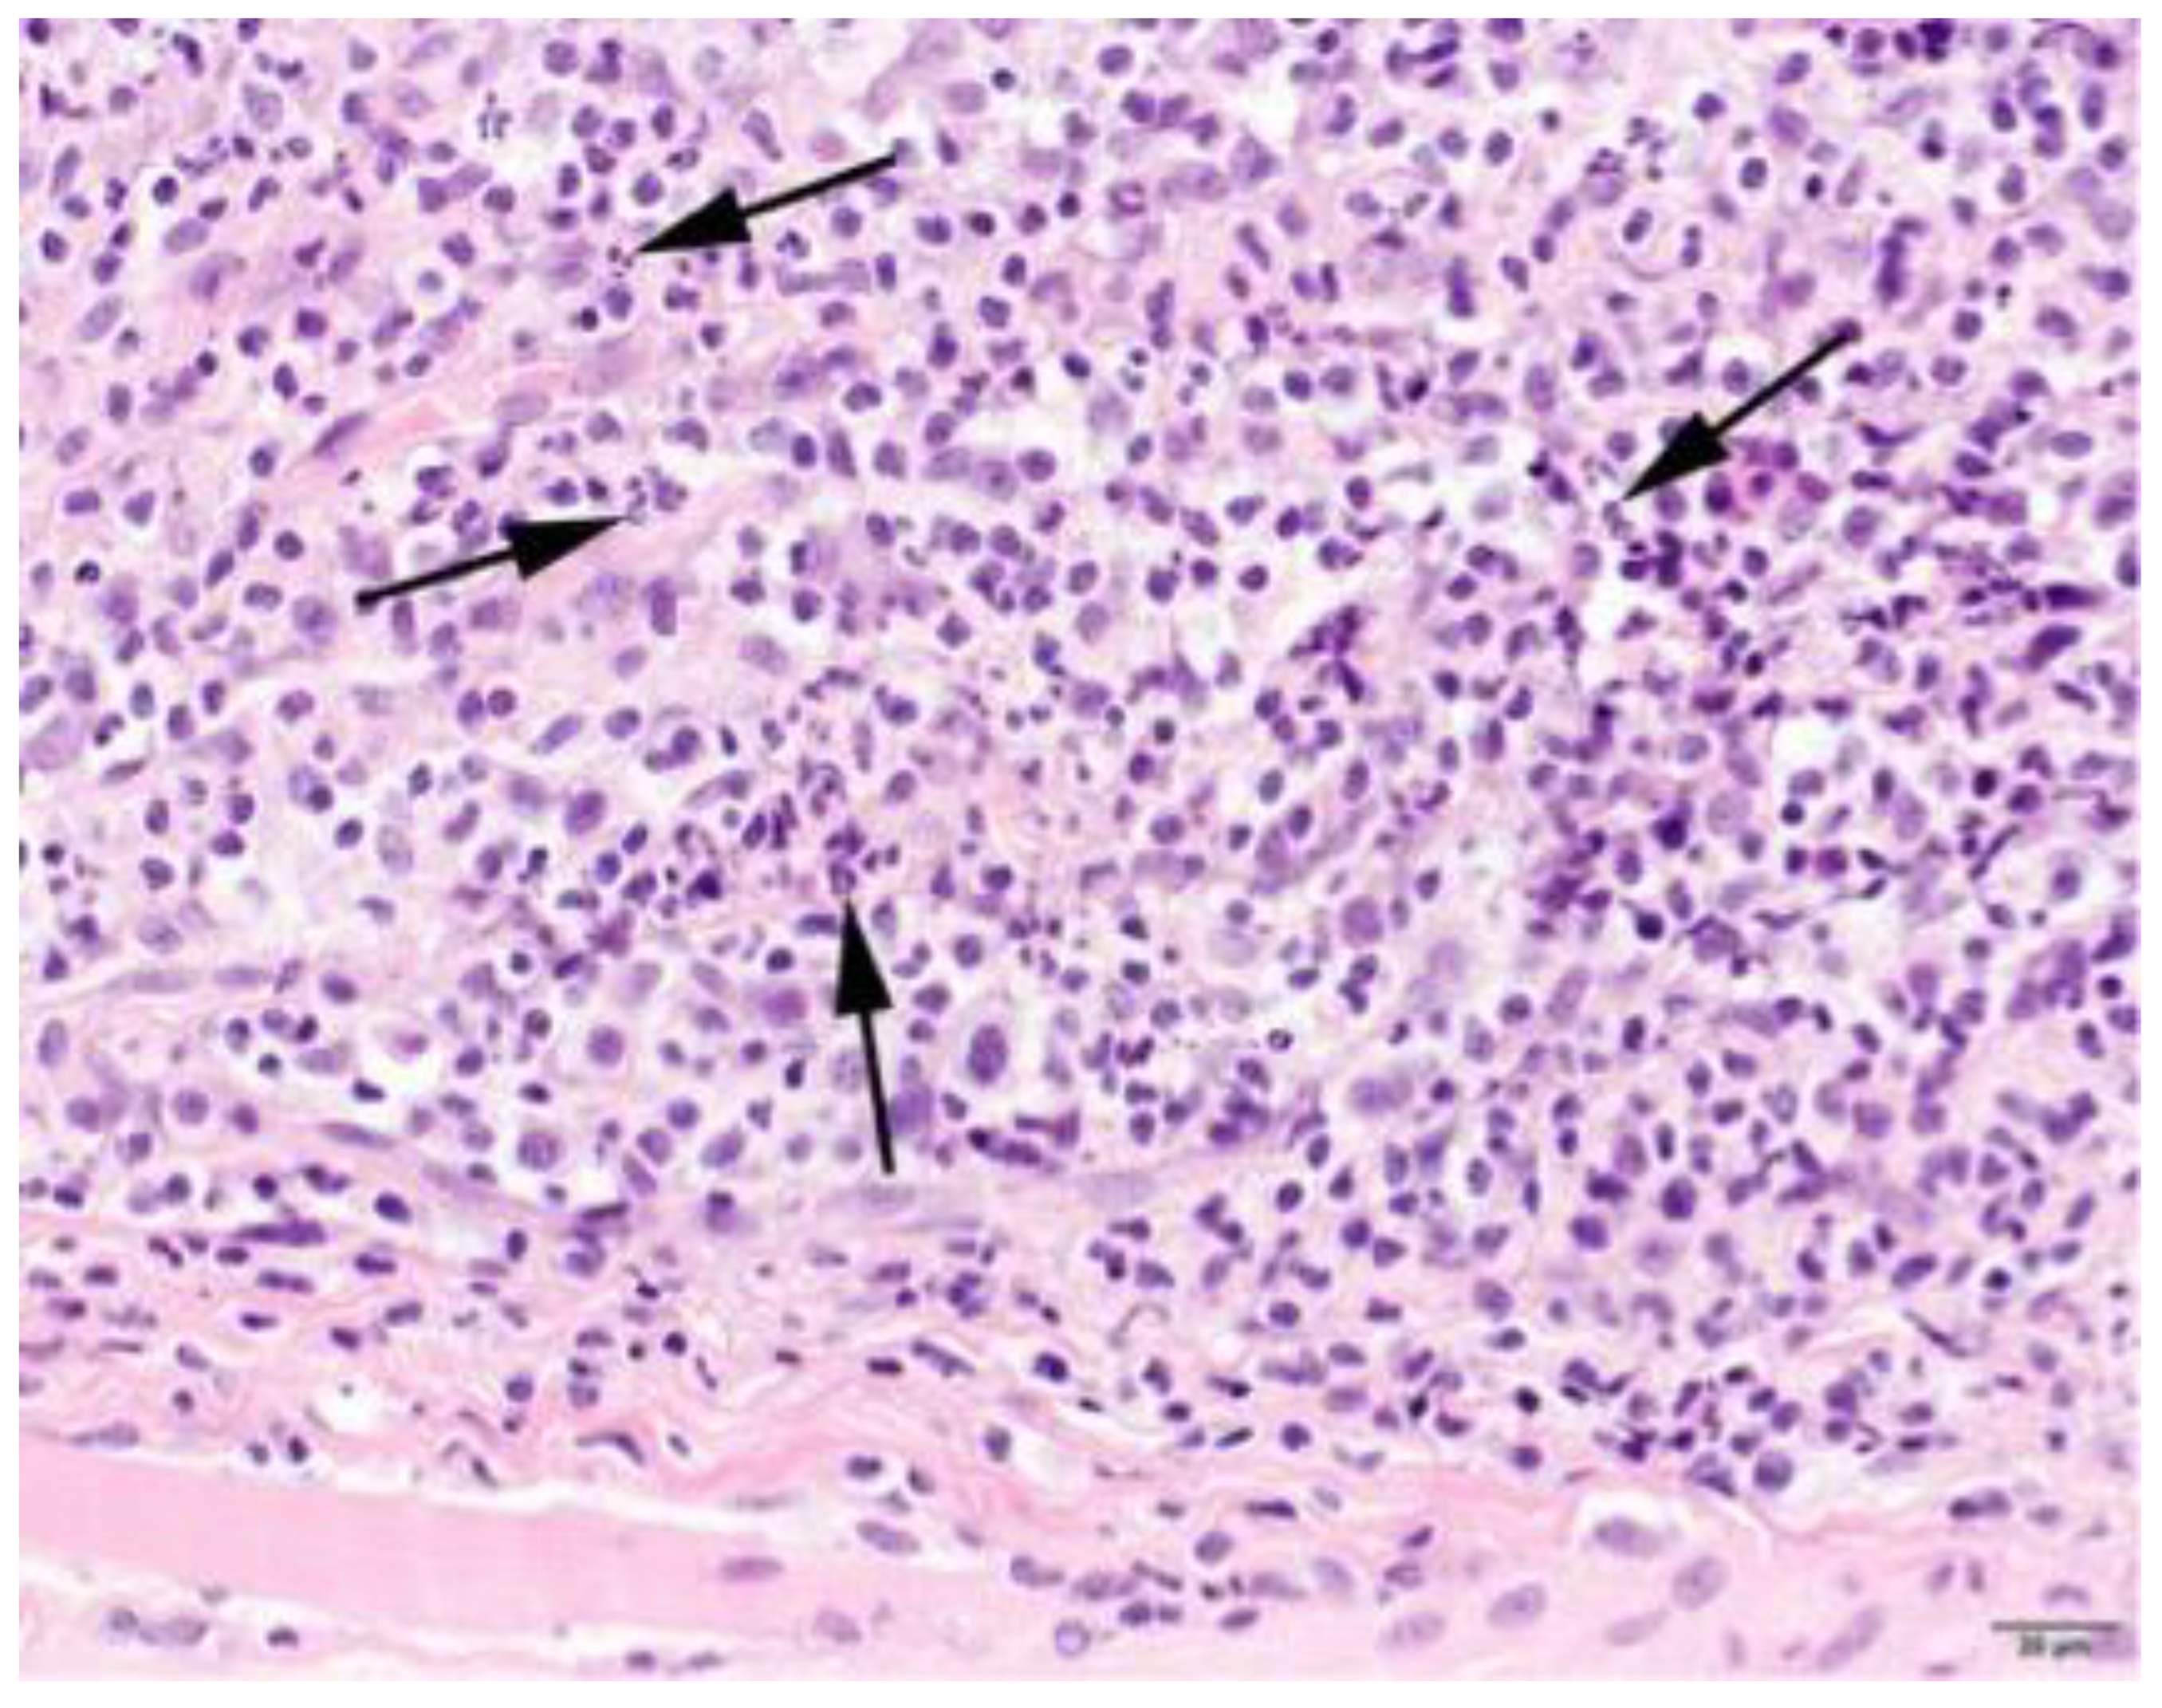

3.4. Histopathology

| Pattern | Expanse | Phase | Location Infiltrate | ||||||

|---|---|---|---|---|---|---|---|---|---|

| Focal | 2 | Mild | 5 | Subacute | 4 | Degeneration | 63 | Endomysium | 27 |

| Multifocal | 63 | Moderate | 13 | Chronic | 29 | Regeneration | 38 | Endomysium and perimysium | 17 |

| Severe | 9 | Atrophic | 25 | Perimysium | 5 | ||||

| Necrosis | 31 | ||||||||

| Fibrosis | 35 | ||||||||

| Characterization of Infiltrate and Severity | |||||||||

|---|---|---|---|---|---|---|---|---|---|

| Lymphocytes | Neutrophils | Eosinophils | Histiocytes | Plasmacells | |||||

| + | 18 | + | 25 | + | 22 | + | 16 | + | 22 |

| ++ | 29 | ++ | 10 | ++ | 8 | ++ | 28 | ++ | 14 |

| +++ | 22 | +++ | 4 | +++ | 6 | +++ | 31 | +++ | 5 |